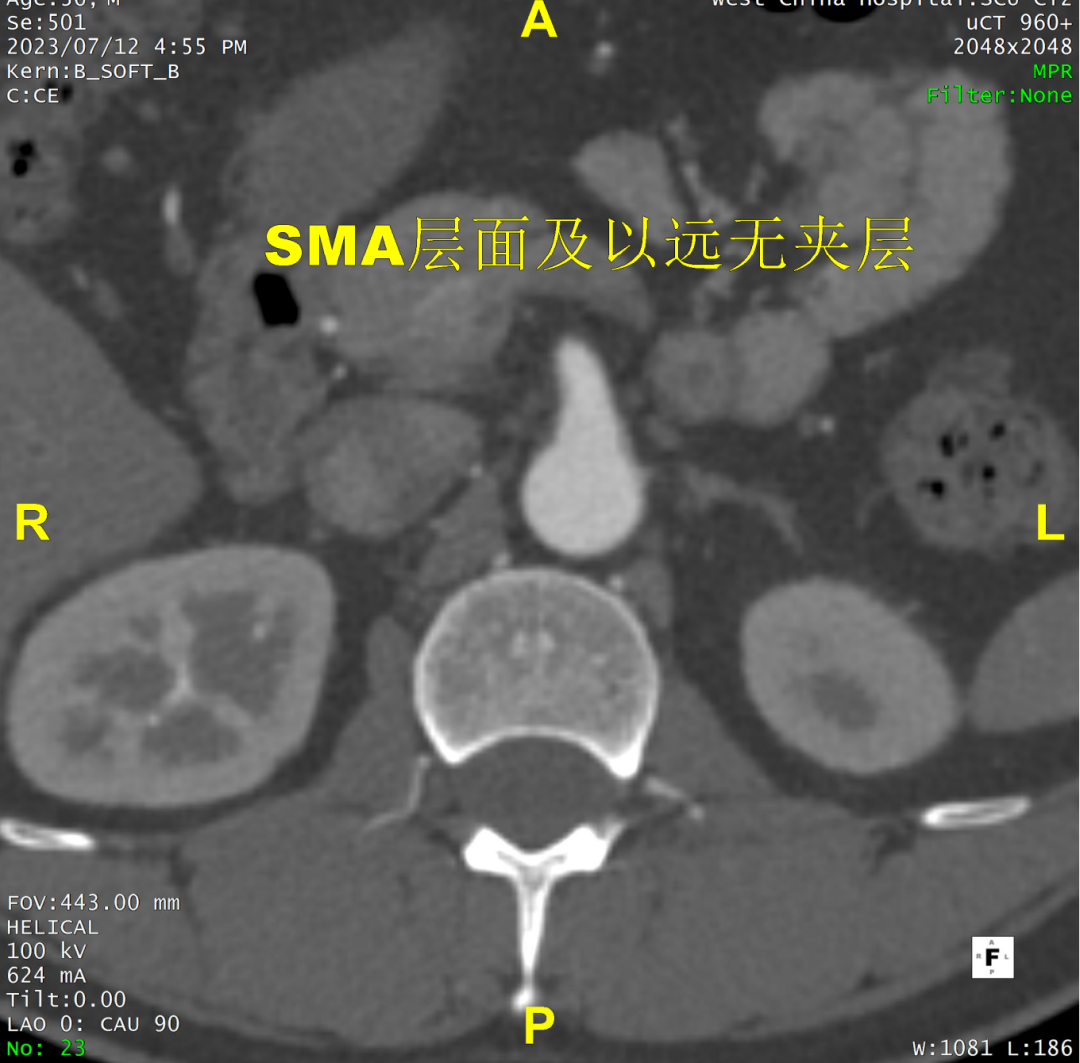

术前CTA评估与测量

术前CTA提示主动脉夹层(Stanford B型,Debake llI型),主动脉弓及降主动脉瘤样扩张,累及左锁骨下动脉起始段,管径最粗约7.4cm,夹层初破口位于降主动脉起始段,向下累及至腹主动脉(约平胸12椎体水平),真腔小,假腔大,腹腔干发自混合腔,肠系膜上动脉、下动脉,双肾动脉均起自真腔,双肾灌注未见差异。

病例特点

1. 弓型陡峭,成角;

2. 自左颈总后缘小弯侧锚定区不足1cm;

3. 巨大破口,约33mm,病变累及至腹腔干平面。